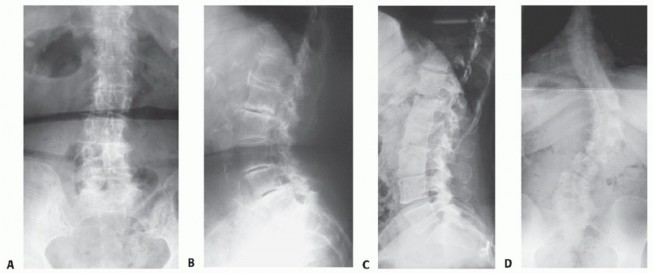

Lumbar degenerative scoliosis may be characterized by loss of lordosis and intervertebral disc height as well as listhesis in the anteroposterior, lateral, or rotary direction (FIG 1A,B).

Long curves, typically the result of a preexisting spinal deformity, may involve the entire thoracolumbar spine and may be associated with a significant rotational component (FIG 1C,D).

FIG 1 • A,B. Degenerative lumbar scoliosis, with mild degree of deformity, in PA (A) and lateral (B) radiographs. Small lateral, rotary, and anterolistheses are seen, with significant loss of disc height, osteophyte formation, and subchondral sclerosis. The coronal deformity is limited to the lumbar region. C,D. A longer scoliosis, and of more significant degree, involving the lumbar and thoracic regions, and associated with rotational deformity, is shown in PA (C) and lateral (D) radiographs.*